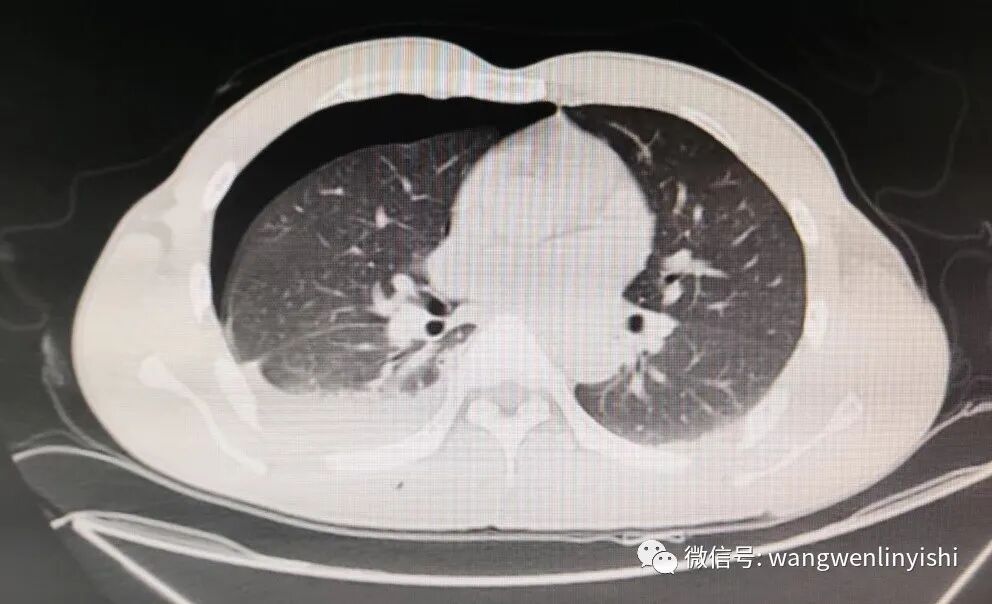

今天的患者为男性,35岁,因外伤3小时急诊入院。患者入院前3小时从高处坠落,右侧胸壁着地,伤后局部剧烈疼痛,呼吸时加重,伴呼吸困难。入院查体:右侧胸壁下部大面积皮肤擦伤,局部有明显压痛,骨擦感明显。右侧呼吸音明显减弱。身体其他部位未见外伤。术前行影像学检查,提示右侧第6、7、8、9、10肋骨骨折,所有五条肋骨在腋中线到腋前线之间均有一处骨折,全部离断,第9、10肋骨在后肋靠近脊柱旁均有粉碎性骨折,骨折端完全离断。右侧血气胸。术前诊断为重度胸外伤,肺裂伤,多根多处肋骨骨折,血气胸。

患者诊断明确,有手术指征。经成分术前准备,今天上午急诊手术。左侧卧位,先采用右侧腋前线到腋中线之间的斜切口,切开胸壁各组织,经第6肋间入胸。术中见胸壁组织间大量淤血,右侧第6、7、8、9、10肋骨骨折,腋前线与腋中线间存在单处骨折,骨折端完全断裂。经胸腔内探查骨折部位,发现第9、10肋骨在后肋靠近脊柱旁有粉碎性骨折,骨折端刺向胸腔内。右侧胸腔内约有500ml鲜红血液,右肺下叶有3处裂口,裂口大小均为1CM左右,有鲜血和气体溢出。清除胸腔内积血,冲洗胸腔后,直接对肺部裂口做缝合。以5条MatrixRIB分别对右侧第6、7、8、9、10肋骨中段的骨折做固定,均采用钢丝进行固定。固定完毕后,于右侧脊柱旁做切口,充分游离周围结构,显露第9、10肋骨后肋处的骨折。用两条MatrixRIB做固定,依然采用钢丝进行操作。骨折固定完毕后,反复冲洗胸腔和术野,右侧胸腔内和术野分别放置引流,逐层关闭切口,手术结束。

今天的患者为严重的胸外伤患者。多根多处肋骨骨折直接导致肺部裂伤,形成血气胸。由于后肋骨折距离前方骨折部位较远,没有形成浮动胸壁,没有出现反常呼吸,但由于有胸腔内脏器损伤,伤情严重,因此不得不做开胸探查,对肺部损伤做处理。